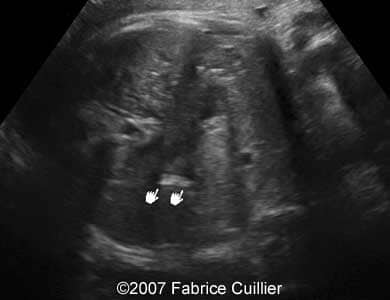

A 30-year-old patient, G3P2, was referred to our clinic at 36 weeks of gestational age after hyperechoic foci were seen in the fetal gallbladder on ultrasound. 13- and 22-week sonographic examinations were unremarkable. The 36-week ultrasound evaluation was normal except for an elongated echogenic mass seen in the gallbladder (Images 1A, 1B, 1C, 1D). Neither ascites nor hydrops were seen. The gallbladder appearance was identical on sonographic re-evaluation at 37 weeks GA (Images 3A, 3B). At 38 weeks of gestational age, a healthy female infant weighing 3200 g was born. There was no evidence of hematologic incompatibility, sepsis, or jaundice. Laboratory values including those for the cystic fibrosis gene, hemoglobinopathy, and liver functions were normal. On the fifth day of life, ultrasound was performed, showing a gallbladder of normal size containing several gallstones (Images 5A, 5B, 5C, 5D).

Images 3A, 3B. Sonogram obtained at 38 weeks of gestational age showing multiple small echogenic foci in the fetal gallbladder.

3A

3B